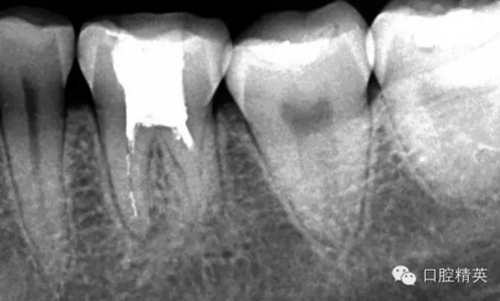

這個(gè)病例是我準(zhǔn)備分根的病例,保留近中根,曾在外院做過(guò)干尸長(zhǎng)達(dá)數(shù)十年。8號(hào)挫疏通時(shí)近舌根堵,近頰未找到。在這個(gè)病例中首先要知道是為什么根管難以疏通,首先是長(zhǎng)時(shí)間的干尸,和患者年紀(jì)較大根管逐漸變窄,根管道路可能會(huì)出現(xiàn)堵塞,在這張病例中我能知道的是稍有不慎就會(huì)形成臺(tái)階,從而導(dǎo)致根管堵塞加重,更加難以疏通。